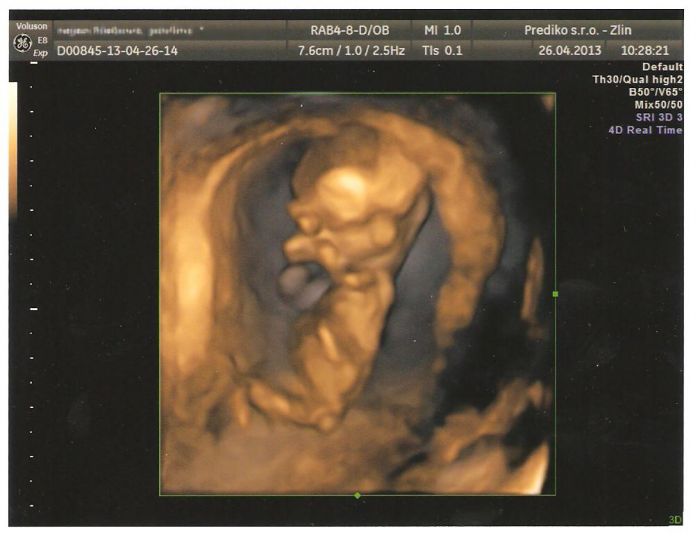

Autor: KlaraN 26.4.2013 v 10:16

Já jsem právě nevěřila mému doktorovi, protože mi zanedbal jedno vyšetření a já jsem měla strach, tak jsem si to sice musela zaplatit, ale vůbec toho nelituji, ultrazvuk na Genetice v Českých Budějovicích a můžu to všem jen doporučit, protože to co zkoumali tam, mi nikdy doktor nedělal, měřily průměr, hlavy, bříška, nožiček, na rty se mi koukaly, jestli nemá roštěp, prohlížely mi srdíčko jestli má všechny komory, no byla jsem naprosto v šoku a zároveň šťastná.